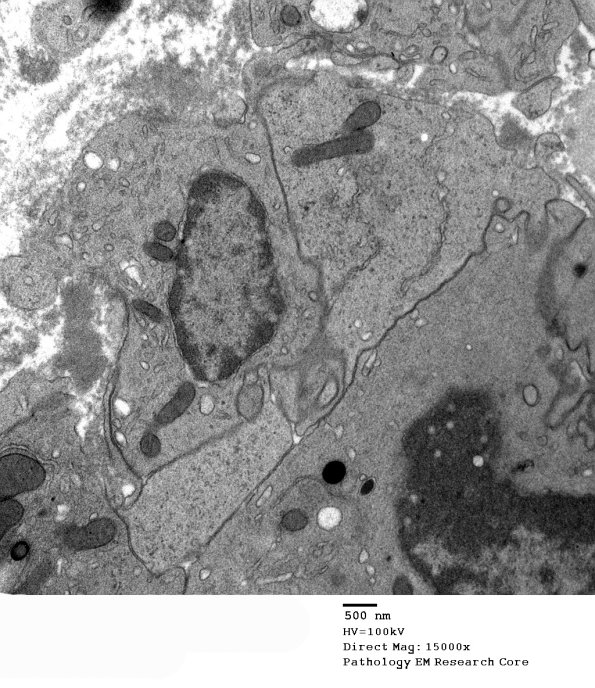

Epithelioid histiocytes do not contain the autophagosomes that dominate the appearance of macrophages although they are derived from the same cell lineage. (electron micrographs)